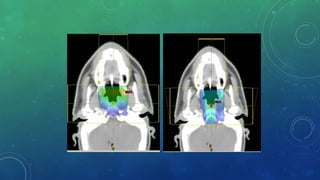

MULTILEAF COLLIMATOR:

โ€ข Multileaf collimators are a bank of large number of collimating blocks or leaves

โ€ข Can be moved automatically independent of each other to generate a field of any shape.

โ€ข 40 pairs of leaves or more having a width of 1 cm on less (projected at the isocenter).

RATIONALE:

* To improve efficiency of treatment delivery

over Conventional Radiotherapy by the

use of Conformal radiotherapy

* To make delivery of 3DCRT

or IMRT possible